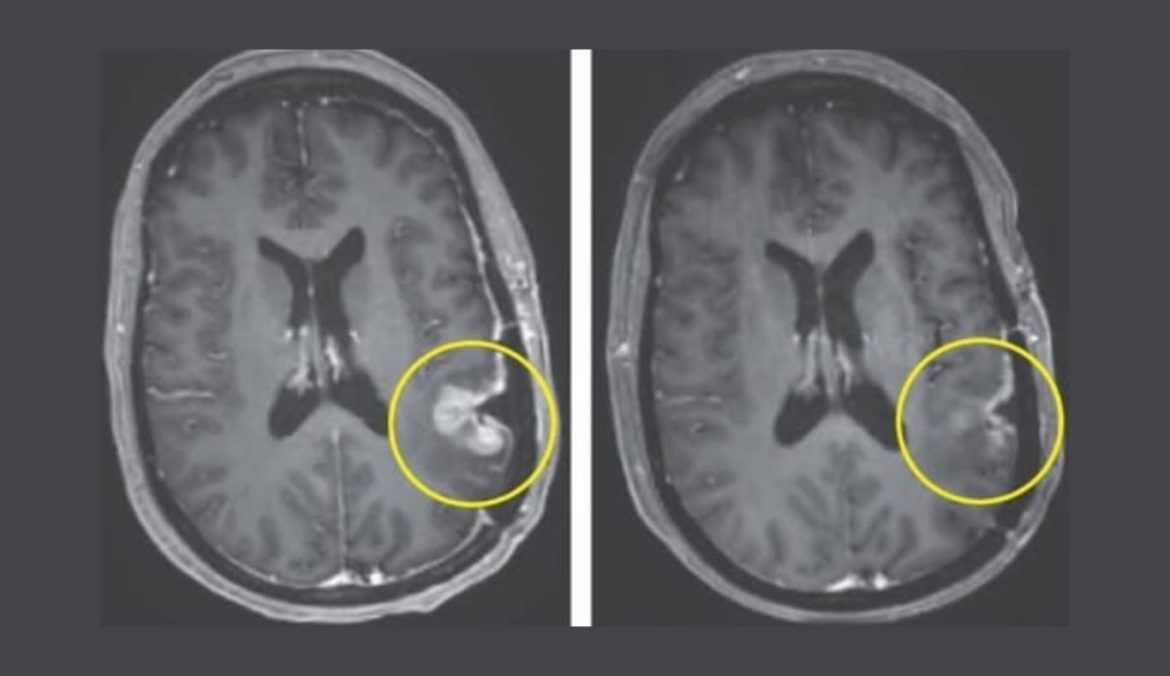

পরীক্ষার এক অবিশ্বাস্য ঘটনায় দেখা গেছে, এক রোগীর টিউমার ইনফিউশনের মাত্র পাঁচ দিনের মধ্যেই নাটকীয়ভাবে সঙ্কুচিত হয়ে প্রায় অদৃশ্য হয়ে যায়। আরেকজন রোগীর টিউমার ৬০ শতাংশ পর্যন্ত ছোট হয় এবং ছয় মাস পর্যন্ত স্থিতিশীল থাকে — যা সাধারণত কয়েক সপ্তাহের মধ্যেই আবার ফিরে আসে।

যদিও পরবর্তীতে টিউমার কিছুটা ফিরে এসেছে, গবেষকরা একে “অভূতপূর্ব প্রতিক্রিয়া” হিসেবে আখ্যা দিয়েছেন এবং বলছেন, এটি ভবিষ্যতে দীর্ঘস্থায়ী এমনকি সম্পূর্ণ নিরাময়যোগ্য থেরাপির পথ খুলে দিতে পারে।